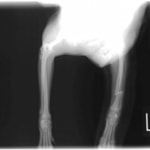

症例3:キルシュナーワイヤーのピンニングによる整復

ペルシャ猫 11ヶ月齢 雄

他院にて左大腿骨遠位の成長板骨折(salter-harrisⅠ型)が認められており、治療相談を目的として来院。当院にて、キルシュナーワイヤーを用いたピンニングにより骨折部位の整復を行いました。術後の経過は良好で、現在も経過観察中です。

術前レントゲン

術後レントゲン